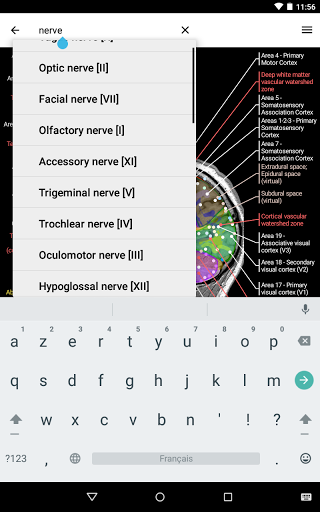

e-Anatomy memiliki lebih dari 26.000 gambar yang berisi serangkaian gambar dalam tampilan aksial, koronal, dan sagital serta radiografi, angiografi, gambar diseksi, bagan anatomi, dan ilustrasi. Semua gambar medis diberi label dengan cermat, lebih dari 967.000 label tersedia dalam 12 bahasa termasuk Terminologia Anatomica Latin.

- Gulir set gambar dengan menyeret jari Anda

- Perbesar dan perkecil

- Ketuk label untuk menampilkan struktur anatomi

- Mudah menemukan struktur anatomi berkat pencarian indeks